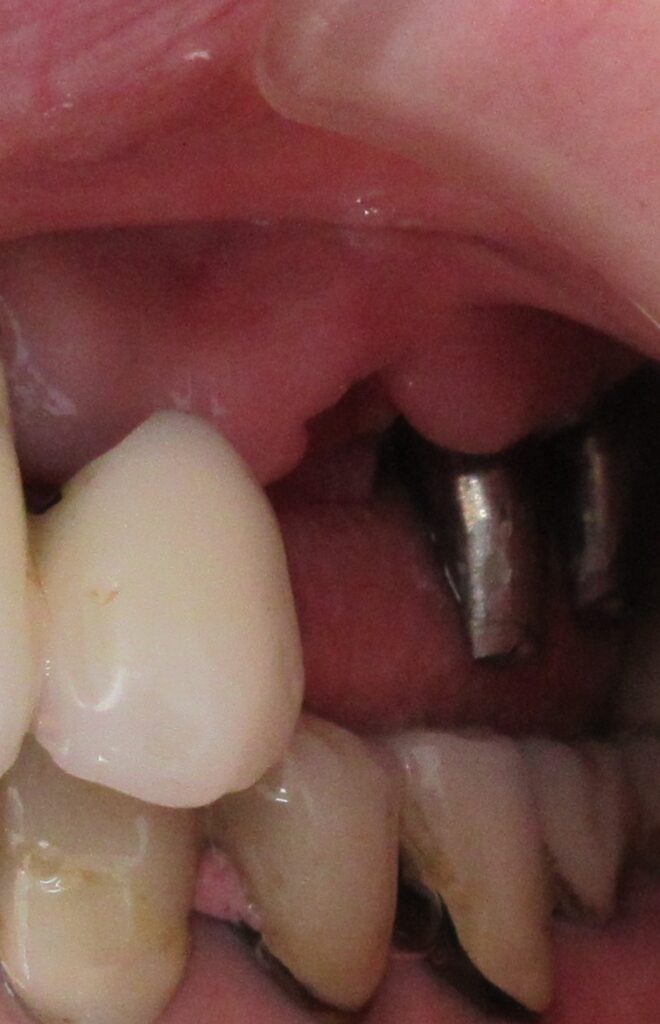

今回の患者様はインプラント植立を希望され、左上3番目の植立が決まりました。

麻酔が効いている事が確認されると、すぐにオペ開始です。

まずは歯茎から骨の部分までを穴開けパンチの要領で穴を開けていきます。

くりぬいた部分の歯肉を取り除き、次は骨に穴を開けていきます。

ドリルの先端を細い物から徐々に大きい物に変えながら、植立するインプラント体のネジの部分を除いた胴の部分の太さに合わせた大きさの穴を開けていきます。

開けた穴に、専用道具を使ってネジを締めるように長さ2センチ程のインプラントを骨に埋め込んでいきます。

しっかりとインプラント埋め込まれた後は、動揺がないか、噛んだ時に当たらないかなどを確認して、最後にパノラマ写真を撮影して今回のオペは終了となりました。